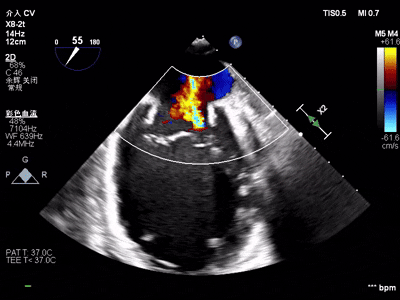

【术中操作(含关键步骤超声)】

鉴于患者术前心功能差、多支架植入的特殊情况,手术全程需兼顾“精准操作”与“保护心功能”双重要求:在全麻与经食道超声的协同引导下,团队先突破心功能受损导致的术野稳定性难题,稳步经心尖建立手术轨道与输送鞘;随后聚焦二尖瓣2偏3区精准置入一枚Ⅱf型夹合器,成功攻占这一解剖位置深、毗邻结构敏感、容错率极低而操作难度陡增的区域。

手术中,主刀术者常青教授稳定发挥,经过严谨的策略思索,挑战超精细微调整与瞬间捕获夹合,逐步逆转反流症状。从显著改善到最终完全消除,全程仅约25min的导管操作时长。在高危病例的严苛挑战下,凸显了团队操作的娴熟度与安全性。